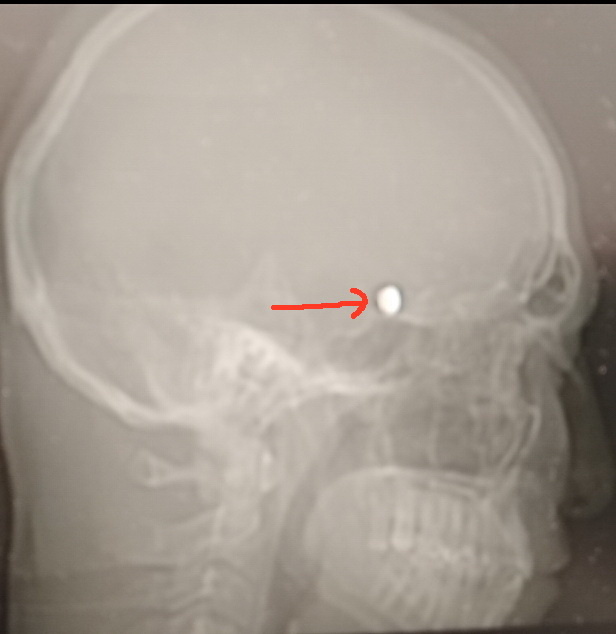

Нет, это не пуля в голове, как многие могли бы подумать. Но случай заслуживает внимания.

В ходе операции было принято решение об экстренной эмболизации разорвавшейся аневризмы. В лучевую артерию введён катетер, по которому в аневризму введено пять платиновых микроспиралей, и жизнь пациента была спасена. «Комочек», состоящий из платиновых микроспиралей, и виден на компьютерной томографии. Он расположен на том месте, где у пациента была опасная для жизни аневризма.